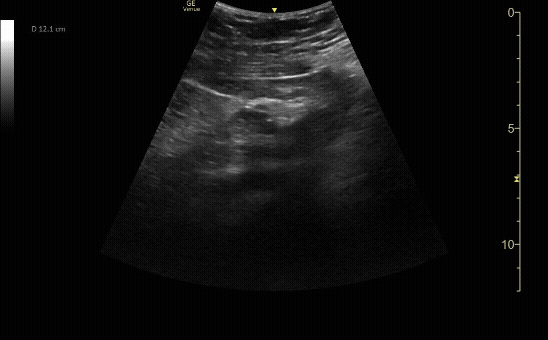

Sagittal view of the uterus with IUP and small subchorionic hemorrhage.

c/o Leslie Cachola MD